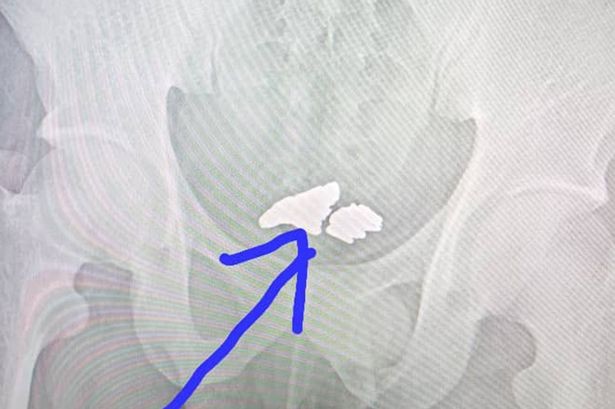

The thief was taken to a local hospital, where, using ultrasound, doctors found inside his body 81 grams of gold. However, operational intervention was not required. An unusual patient was given special means by which the metal after a while came out of it bodies naturally. It seems that this is the case when you can say that gold does not smell.